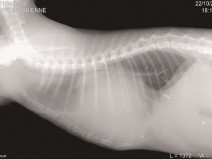

• Les maladies respiratoires et pulmonaires

Etre capable de

• proposer une démarche diagnostique structurée dans le contexte des principales affections des voies respiratoires supérieures et des bronchopathies

En savoir plus

2f14580822ec9e278b6be453894efbcd

Le 13 octobre 2016

AIX-EN-PROVENCE (13100)

Cardiologie

G.E.C.A.

120